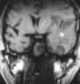

Temporal lobe hematoma

Intracerebral hemorrhage (ICH), also known as cerebral bleed and intraparenchymal bleed, is a sudden bleeding into the tissues of the brain, into its ventricles, or into both. It is one kind of bleeding within the skull and is one kind of stroke.Symptoms can include headache, one-sided weakness, vomiting, seizures, decreased level of consciousness, and neck stiffness. [Source: Wikipedia ]